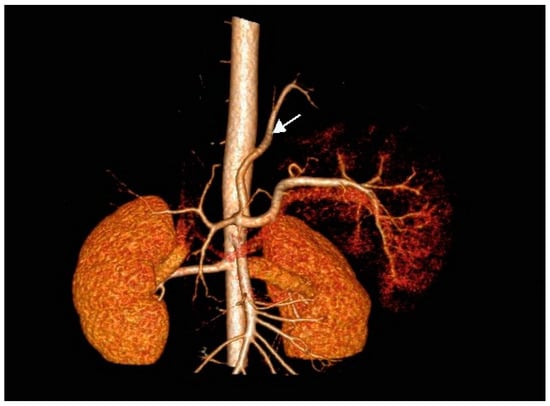

There was no communication of the affected lung parenchyma with bronchi of the left inferior lobe. We noted no further infiltrative changes in the remainder of the left and right lungs. Contrast-enhanced CT scanning with 3D reconstruction showed normal configuration of the thoraco-abdominal aorta, celiac trunk, and renal arteries. The celiac trunk originated from the abdominal aorta at the level of the intervertebral space Th12-L1. The systemic feeding artery (proximal diameter of 5 mm) originated from the celiac trunk. This artery supplied the pulmonary intralobar sequestration in the inferior lobe of the left lung (Figure 2a,b).

Figure 2.

(a) Contrast-enhanced CT scan of the thoraco-abdominal aorta with 3D reconstruction of aorta, celiac trunk, and renal arteries. Note the feeding artery (indicated by arrow) with a diameter of 5 mm supplying the sequestration in the inferior lobe of the left lung (antero-posterior [AP] view). (b) Anomalous artery arising from the celiac trunk (artery indicated by arrow; lateral view).